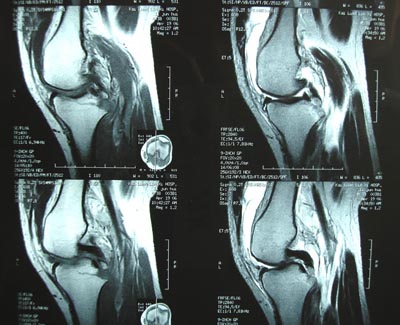

男,45。骑摩托车摔伤左膝肿痛三天,浮髌(+),活动受限。请大家看看片子有问题吗?

现在把ct结果公布,请大家继续讨论。

标题: 现将mri结果公布